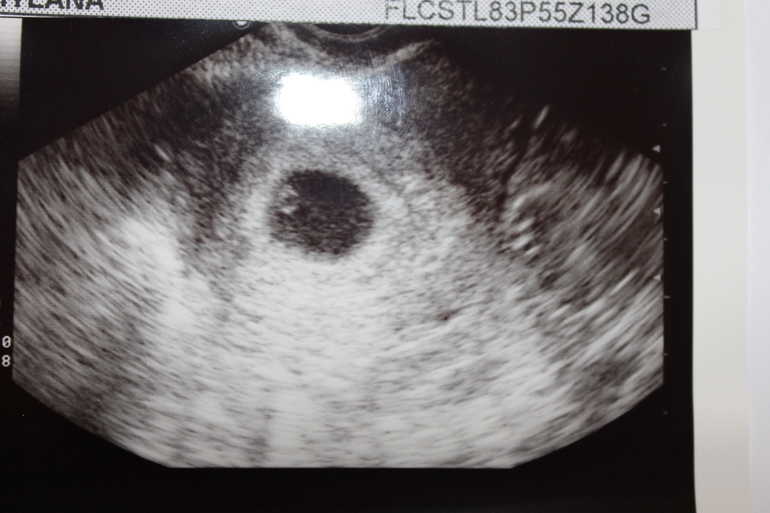

ну вот, земляки) ой, вы ещё махонькие))) но плодное яйцо правильной формы, насколько я вижу....сдать ХГЧ — это правильно, но я бы узи ещё повторила через недельку, чтобы эмбриончика увидеть и сердечко послушать, да и перестраховаться.

посмотрите здесь в комментах я фото узи выставила, сказала гиня,что срок маленький наверное так как плодное яйцо есть, желточный мешочек тоже, это все так переживательно,измотаться можно, у многих я знаю и на 7 недельке не всегда находят, так что ,,,ждемс